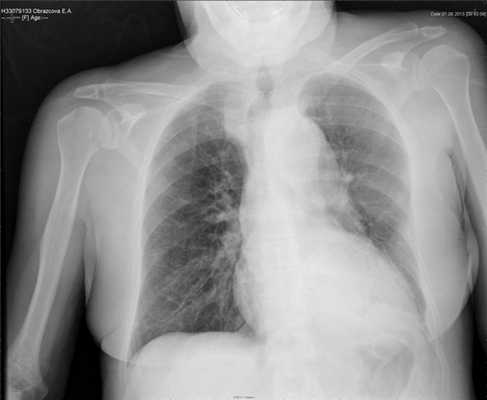

Деканюляция трахеи произведена через 45 дней после трахеостомии. При рентгенологическом исследовании выявлена положительная динамика в виде увеличения прозрачности левого легкого и отсутствия жидкости в левой плевральной полости (рис. 5). Рисунок 5. Рентгенограмма грудной клетки в прямой проекции на 17-е сутки после закрытия раны. Левое легкое без очаговых изменений. Свободной жидкости в плевральных полостях не определяется.